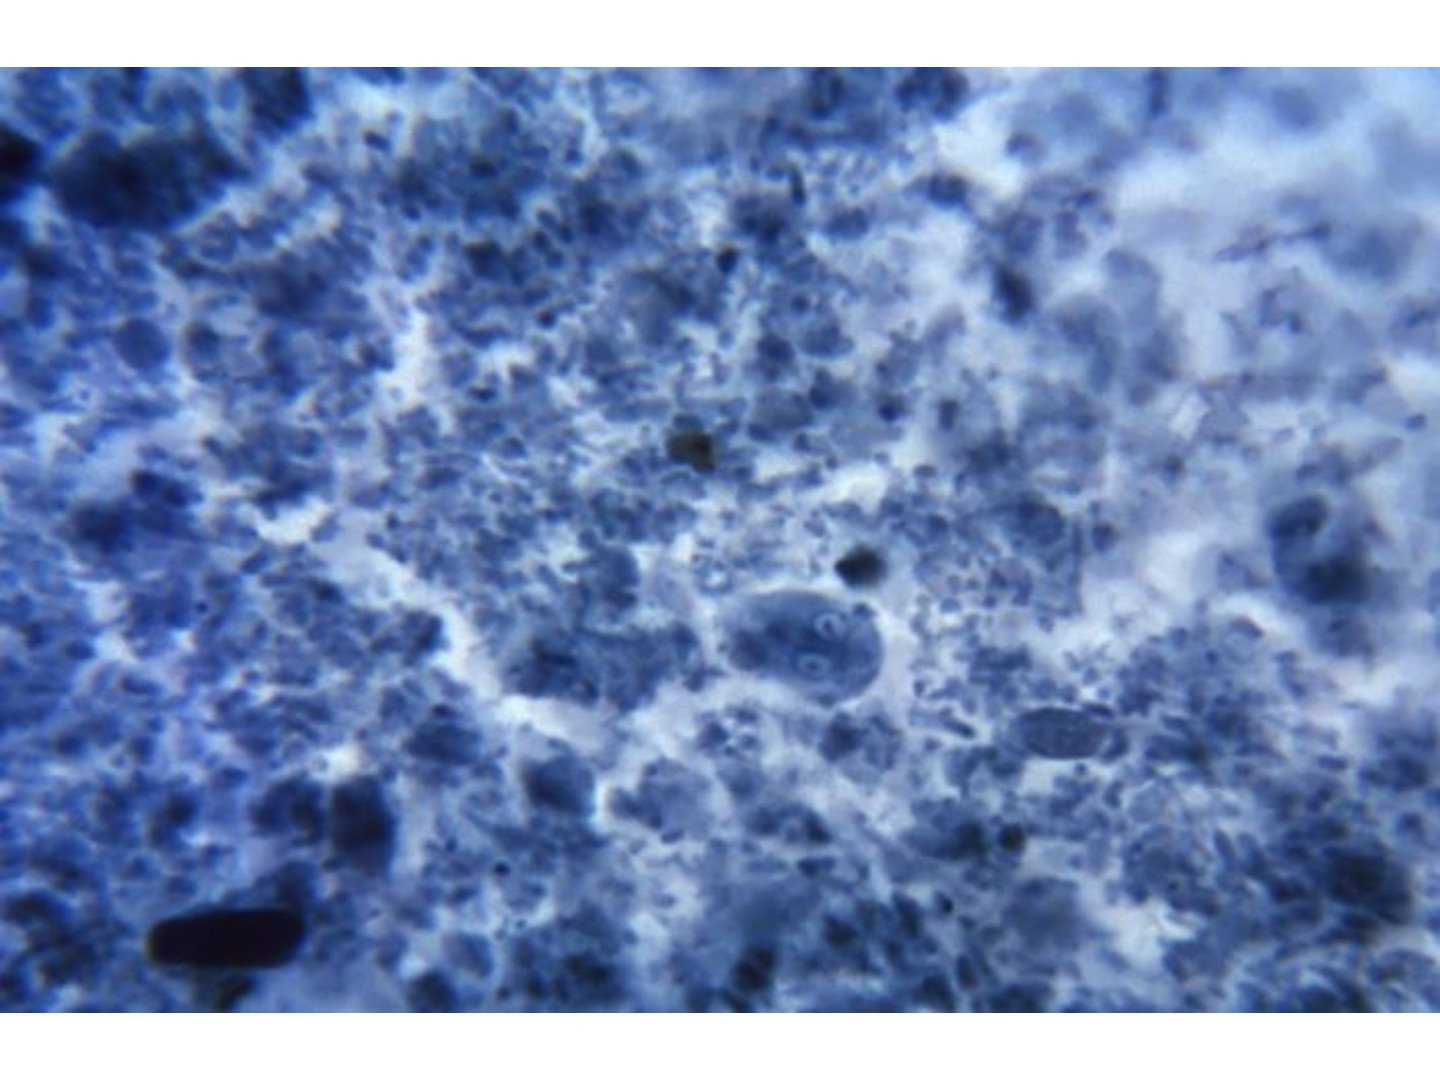

Der Einzeller Giardia lamblia löst die Giardiasis aus (Abb. 25049 und Abb. 250).

Giardien sind Protozoen, d.h. einzellige Eukaryoten (Abb. 25049 und Abb. 250).

Der Einzeller Giardia lamblia löst die Giardiasis aus. Giardien sind Protozoen, d.h. einzellige Eukaryoten.